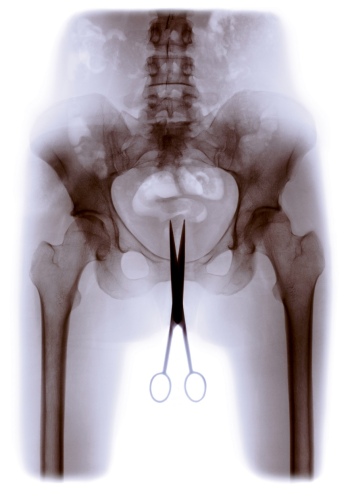

Gender roles, Body images

Cris Bierrenbach, Série Retrato Íntimo (Tesoura), 2003 © Courtesy the Artist